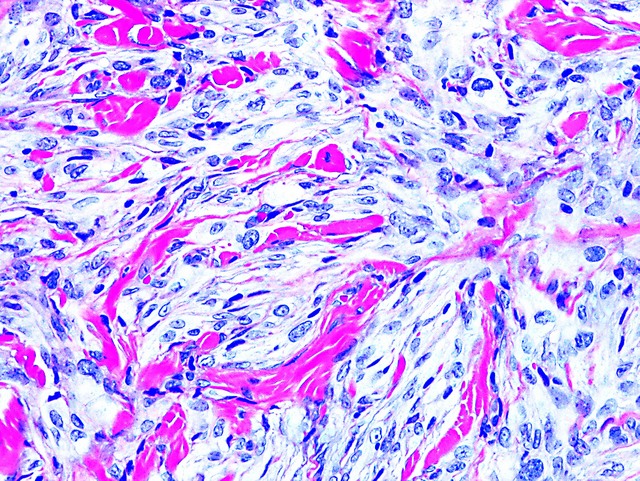

Microscopic (histologic) description

- Cellular, myxoid or mixed subtypes

- Involves dermis or subcutis

- Multinodular mass with myxoid matrix and peripheral fibrosis

- Whorled or focally fascicular patterns of spindled and epithelioid mononuclear cells with abundant cytoplasm, indistinct cell borders

- Margins usually positive; usually occasional multinucleated giant cells

- Variable nuclear atypia

- Median 4 MF / 25 HPF, may have 10+ MF / 25 HPF, may be atypical

Microscopic (histologic) images